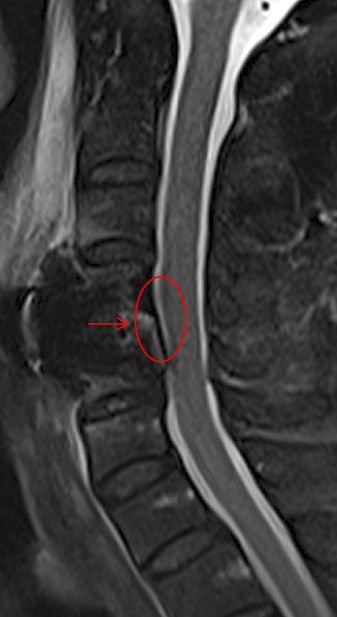

經(jīng)影像結(jié)果顯示

患者的頸4/5節(jié)段椎間盤“出軌”了

向后突出緊緊壓迫著

支配左上肢感覺和運動的神經(jīng)根

被確診為神經(jīng)根型頸椎病

術(shù)前頸椎MR